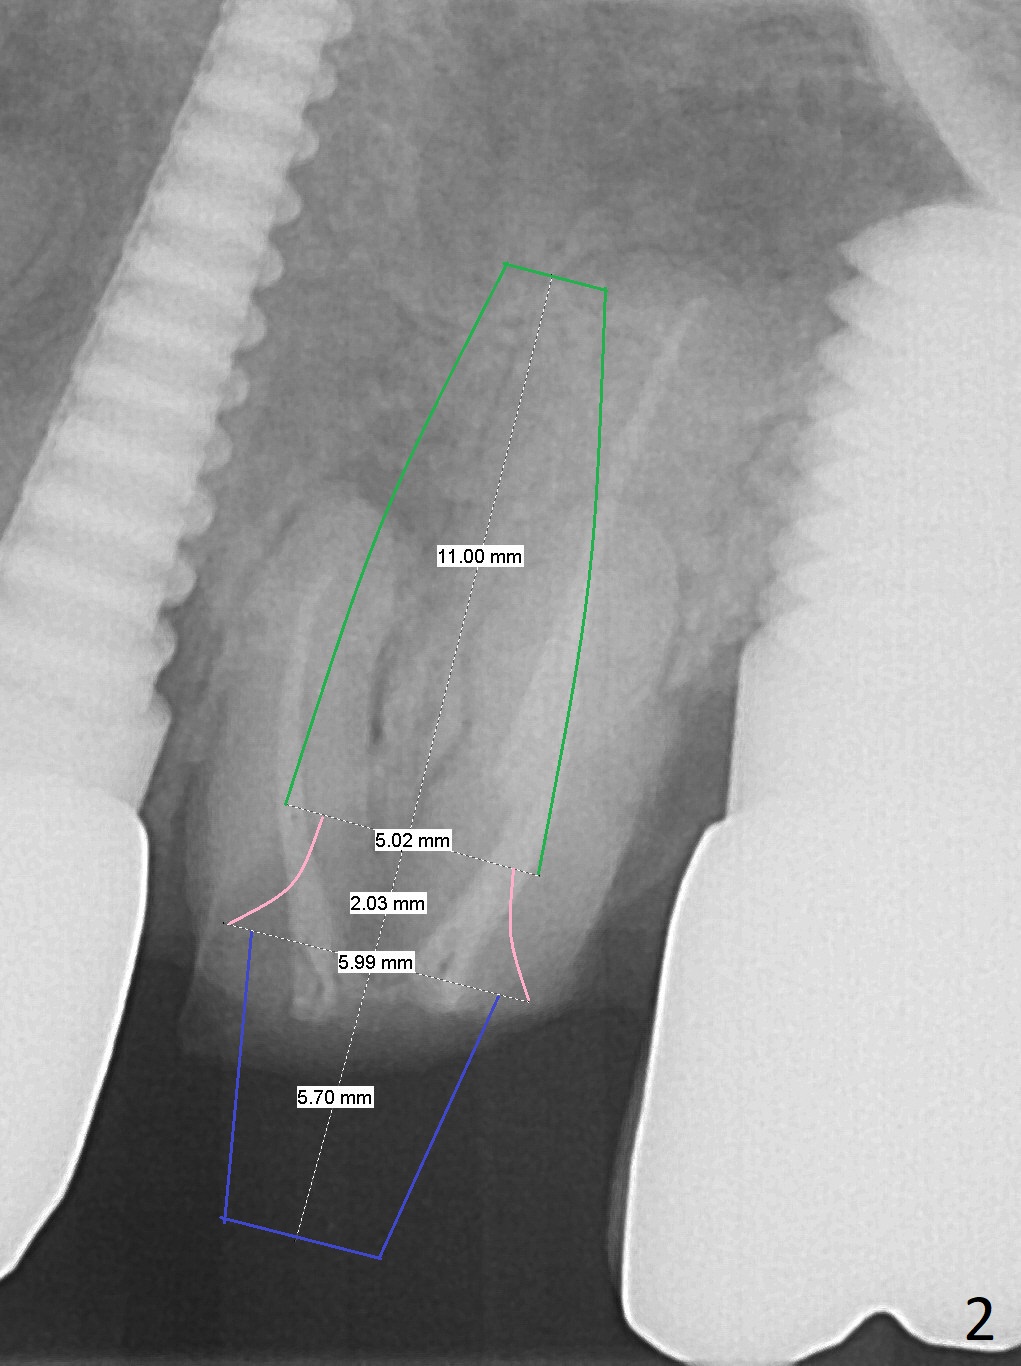

A 70-year-old woman fractures the crown at #14 (Fig.1).  A 5x11 mm implant will be placed at the septum (Fig.2).  Osteotomy depth can be determined using bony (Fig.3 with stopper) or gingival (Fig.4,5 with vision) landmark.  The CT was taken 5 years earlier.  Sagittal (Fig.6) and axial (Fig.7) sections confirm suitability of the 5x11 mm implant for the site.  Prepare surgical handpiece for sectioning the tooth for extraction.  After drills, use Magic Expanders for sinus lift.  Place Vanilla Graft prior to dummy implant(s).  A bone-level implant crown may be easier to be repaired if the proximal contact is not ideal.